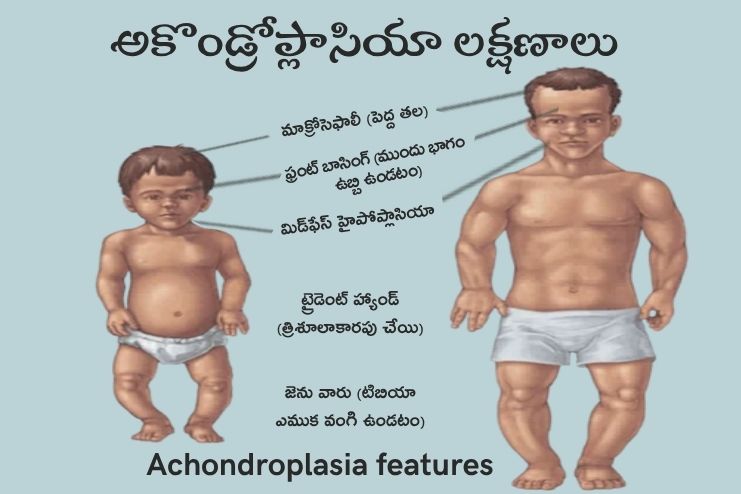

అకొండ్రోప్లాసియా లక్షణాలు? Symptoms of Achondroplasia

- ఎముకలు పొట్టిగా ఉంటాయి (తొడ, పై చేయి).

- చేతులు, పాదాలు పొట్టిగా ఉంటాయి.

- మూడవ మరియు నాల్గవ వేళ్ల మధ్య పెద్ద ఎడబాటు ఉంటుంది.

- గరిష్టంగా 4 అడుగుల ఎత్తు ఉంటారు.

- తల సాధారణం కంటే పెద్దదిగా ఉంటుంది.

- నుదురు ముందుకు పొడుచుకుని ఉంటుంది.

- ముక్కు చదునుగా ఉంటుంది.

- శిశువులలో అభివృద్ధి ఆలస్యం (కూర్చోవడం, పాకడం, నడవడం).